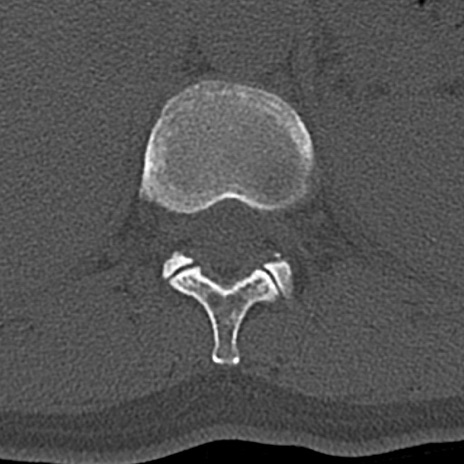

腰椎CT

横断像と矢状断像